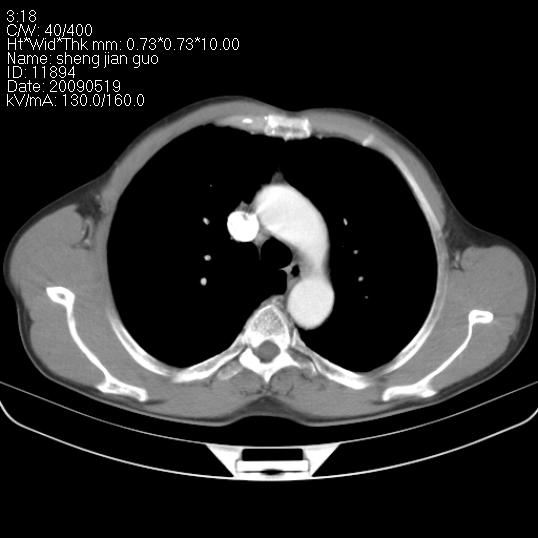

以下是引用zjzjr在2009-5-19 17:25:00的发言:[br]支持楼主考虑,另左肺下叶阻塞性炎症。

以下是引用zhao_bin2008在2009-5-19 17:48:00的发言:[br]支持左肺下叶周围型肺癌并阻塞性肺炎。

以下是引用zsl6918在2009-5-20 7:10:00的发言:[br]左侧中心型肺癌!